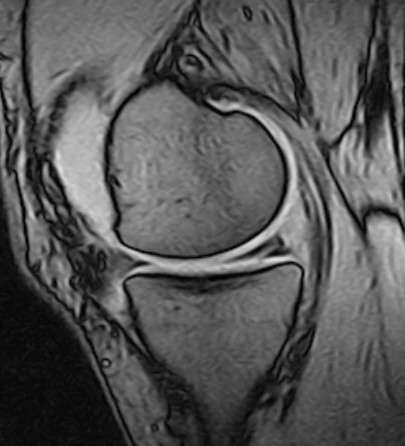

However, degenerative meniscus tears can often be asymptomatic and may appear as incidental findings on MRI without clinical significance (20). The tears occur in degenerate tissue with reduced water content, fewer elastic fibres and increased stiffness, such that an axial load gives rise to shear forces that tear the connections between collagen fibres. The shape of the meniscus changes and its protective function in relation to the articular cartilage is reduced (21). The tears are described as complex (multiple tears), horizontal (Figure 1) or oblique (flap tears), and most often occur in the posterior part of the medial meniscus.

Traumatic meniscus injuries are most often seen in active younger individuals and are often high-energy injuries, not infrequently associated with damage to the anterior cruciate ligament (23). Typical traumatic tears are 'bucket handle'-shaped (longitudinal, vertical (Figure 2, Figure 3), and with the torn part of the meniscus potentially folded over towards the intercondylar eminence), radial, or flap-shaped. Folded bucket-handle tears can restrict both flexion and extension, and early repositioning and suturing are indicated to prevent shrinkage and destruction of the meniscus tissue.

Meniscal root tears are injuries at the site of or close to the posterior attachment of the menisci to the tibia (posterior root tears) (Figure 2) (24). Medial root tears are most often seen in degenerative knees as part of the development of osteoarthritis, and lateral root tears are most often seen in younger patients with damage to the anterior cruciate ligament. Root tears often cause more pain and effusion than other meniscus injuries.